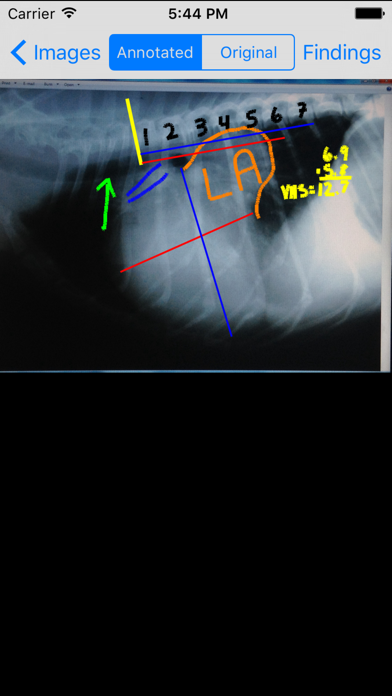

Скриншоты